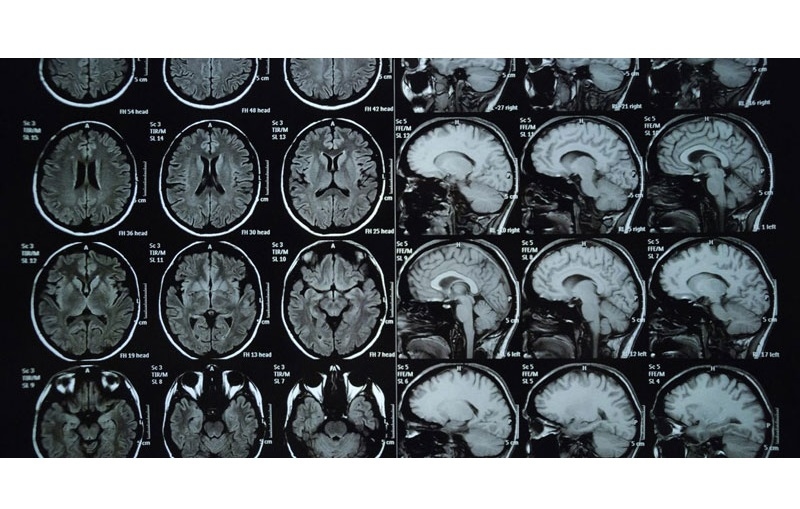

Với khả năng tạo ra hình ảnh chi tiết, rõ nét, MRI không chỉ hỗ trợ phát hiện các khối u, viêm nhiễm, tổn thương thần kinh mà còn giúp theo dõi tình trạng bệnh trong quá trình điều trị, từ đó đưa ra phác đồ điều trị hiệu quả nhất. Cùng tìm hiểu kỹ hơn về quy trình và những trường hợp cần thực hiện chụp MRI vùng đầu cổ.

Chụp MRI đầu mặt cổ là phương pháp chẩn đoán hình ảnh hiện đại, không xâm lấn, không sử dụng tia X hay bất kỳ chất phóng xạ nào, đảm bảo an toàn cho hầu hết các đối tượng. Đây là kỹ thuật giúp bác sĩ phát hiện sớm và đánh giá chính xác nhiều bệnh lý liên quan đến vùng đầu, mặt và cổ.